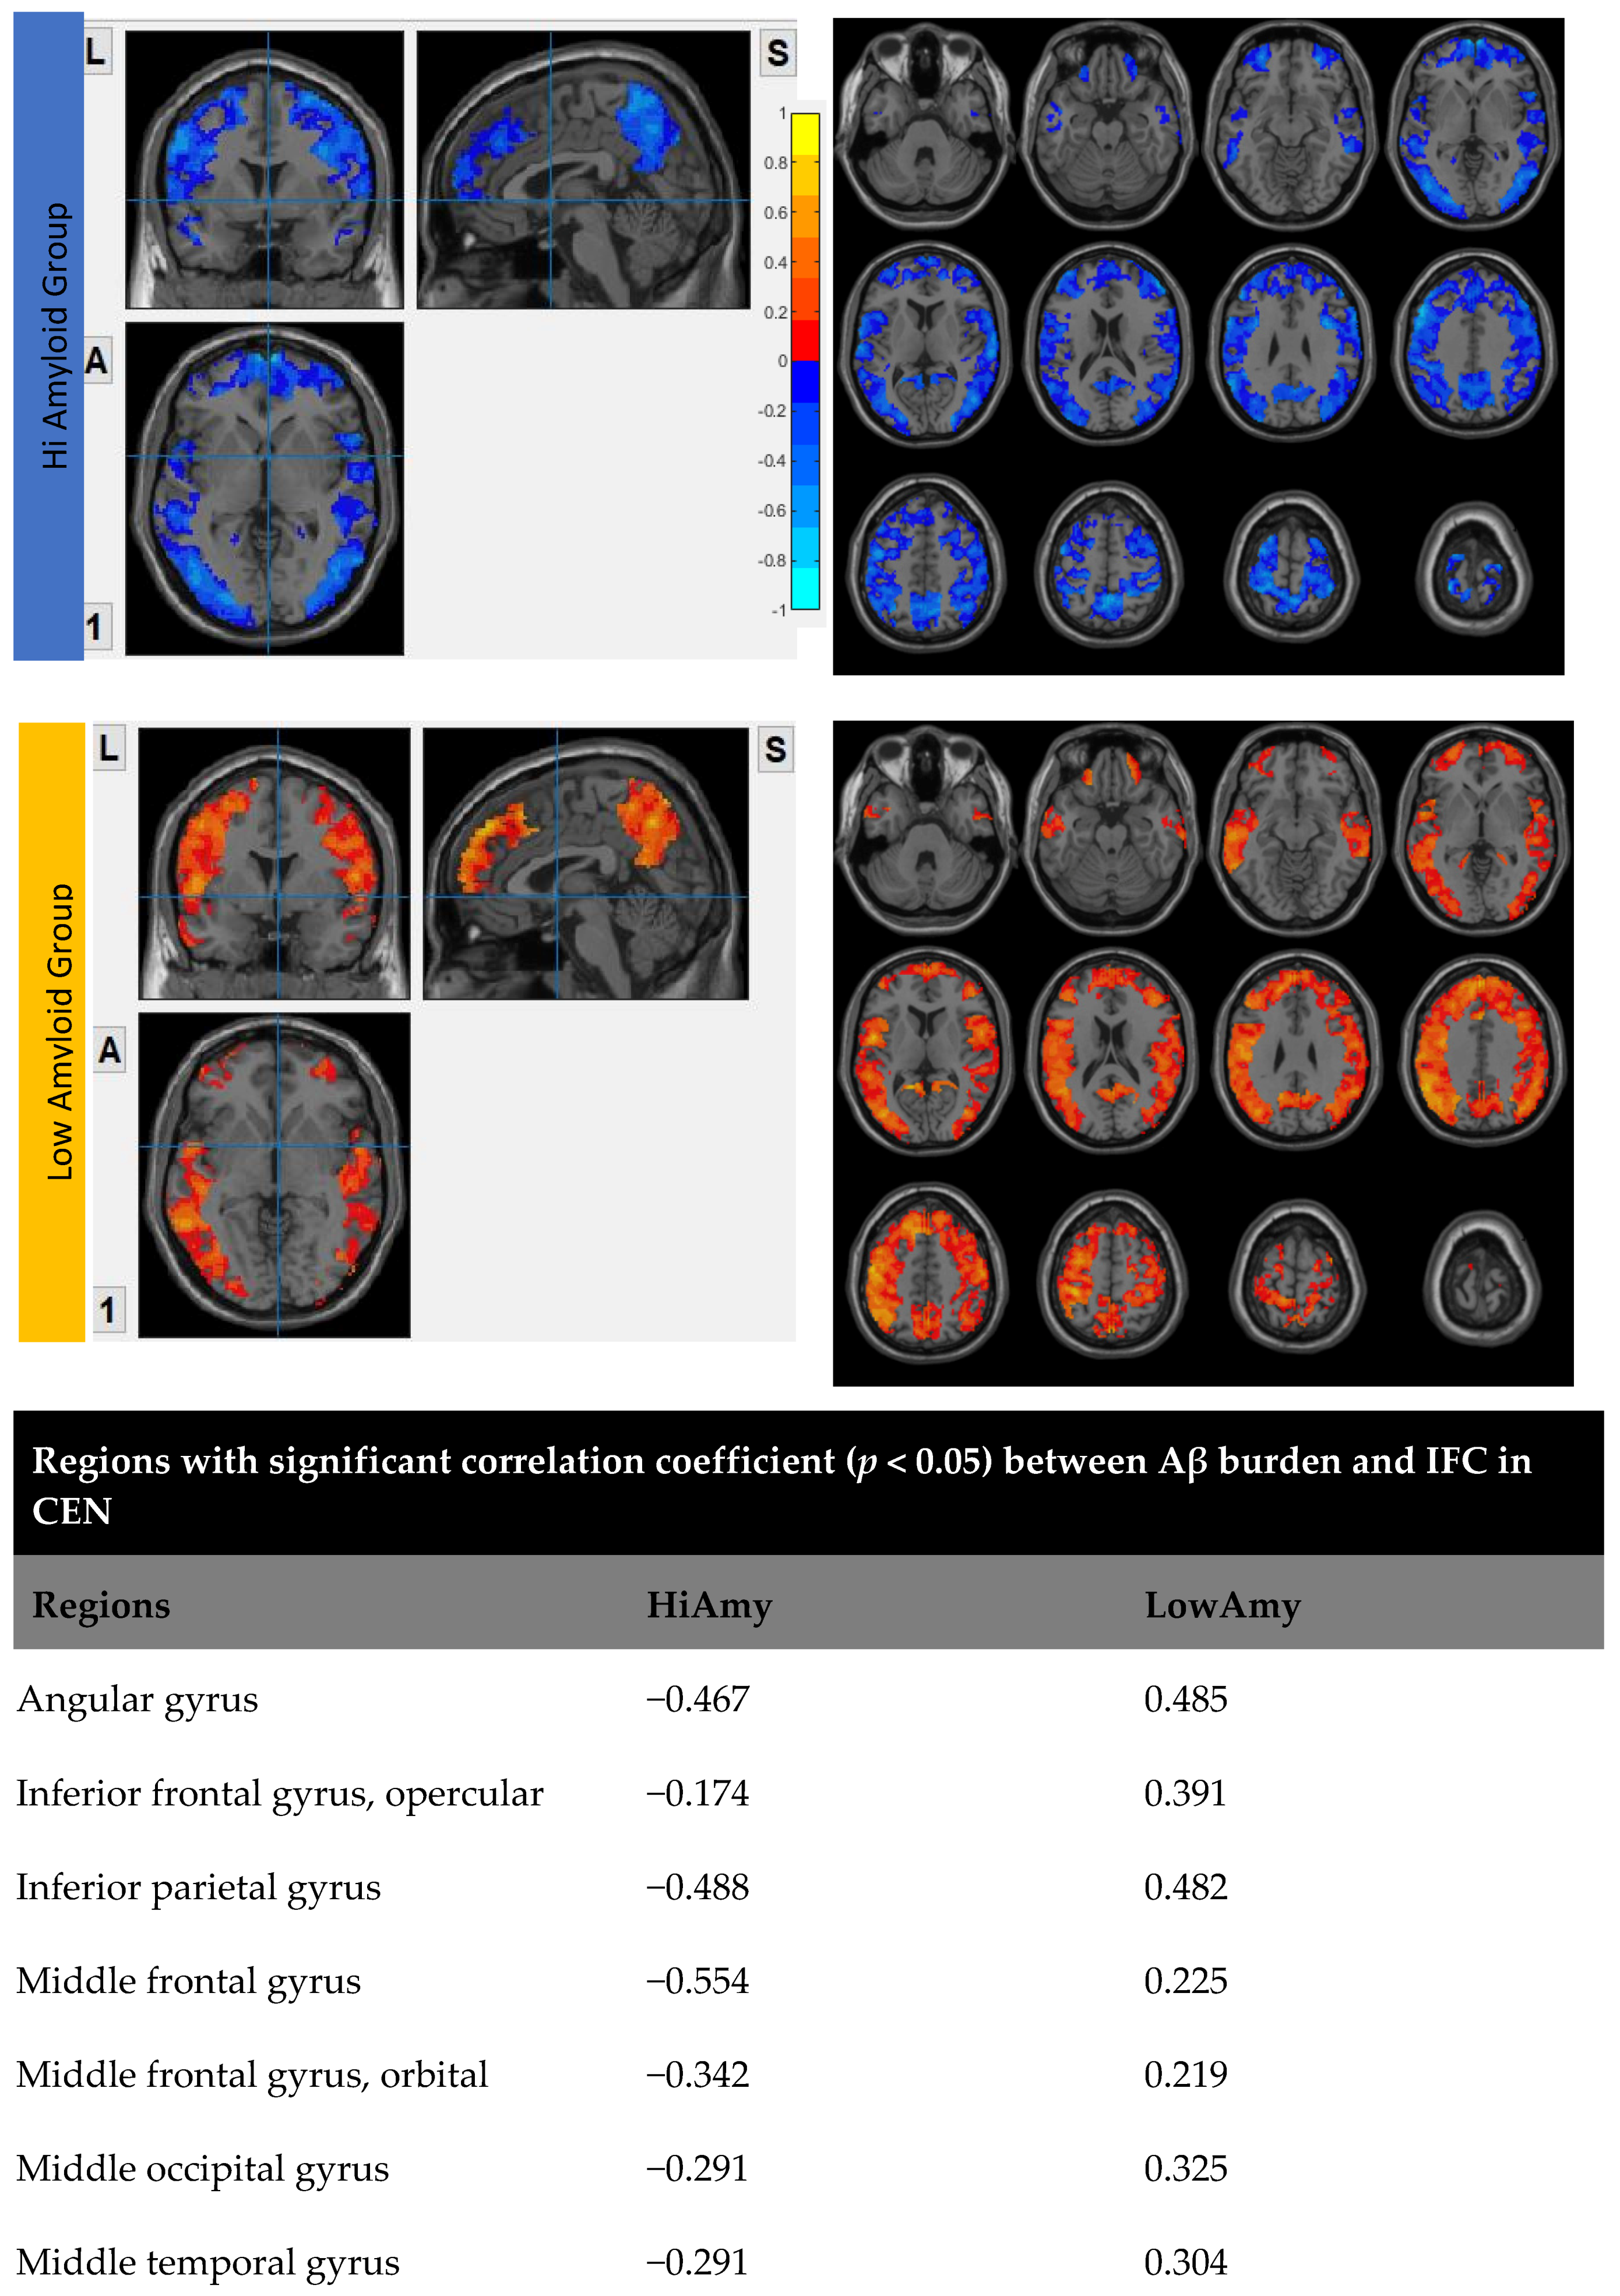

6.3. Interhemispheric Functional Connectivity (VMHC) Maps

7.1. Within DMN